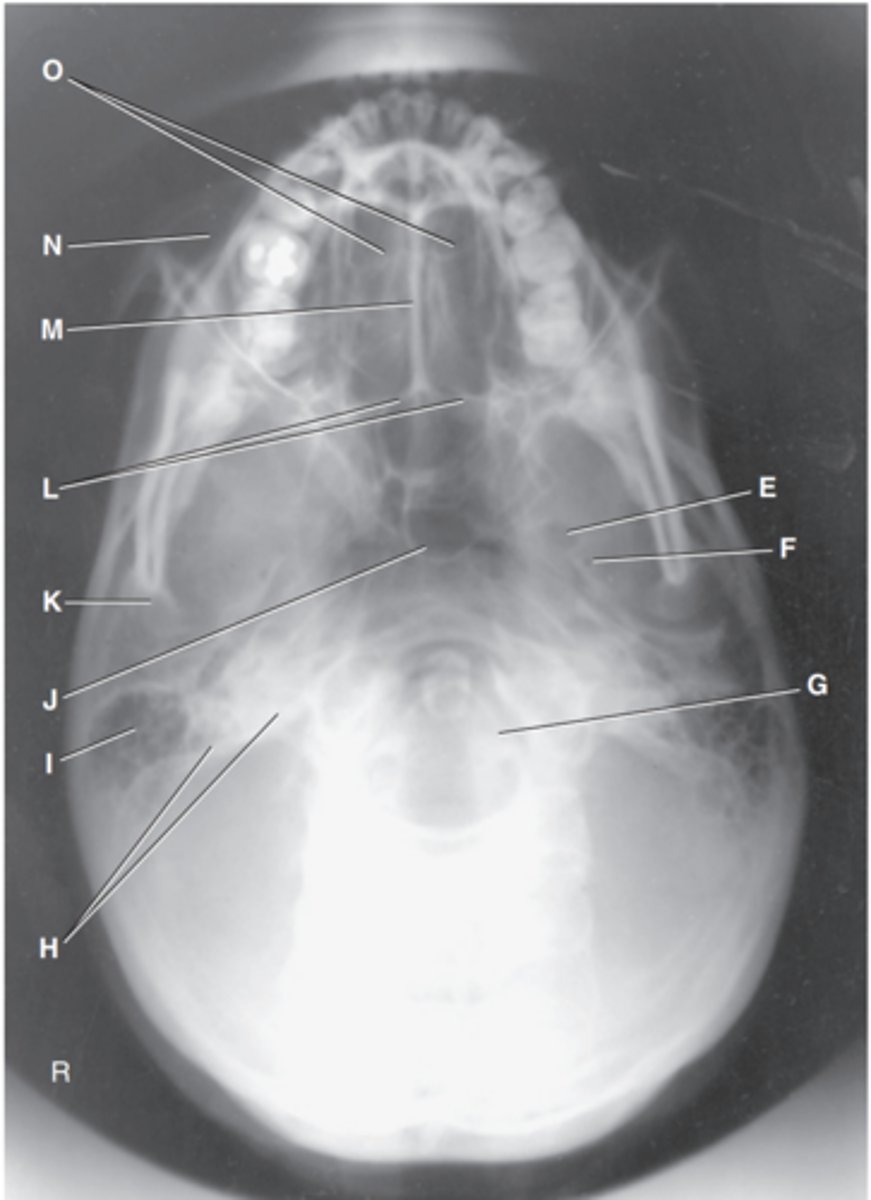

Foramen magnum

Label J

Zygomatic arch

Label A

Palatine process of maxilla

Label B

Horizontal process of palatine bone

Label C

Pterygoid hamulus of sphenoid

Label D

Foramen ovale of sphenoid

Label E

Foramen spinosum of sphenoid

Label F

Foramen magnum

Label G

Petrous pyramid of temporal bone

Label H

Mastoid portion of temporal bone

Label I

Sphenoid sinus in body of sphenoid

Label J

Condyle of mandible

Label K

Posterior border of palatine bone

Label L

Vomer

Label M